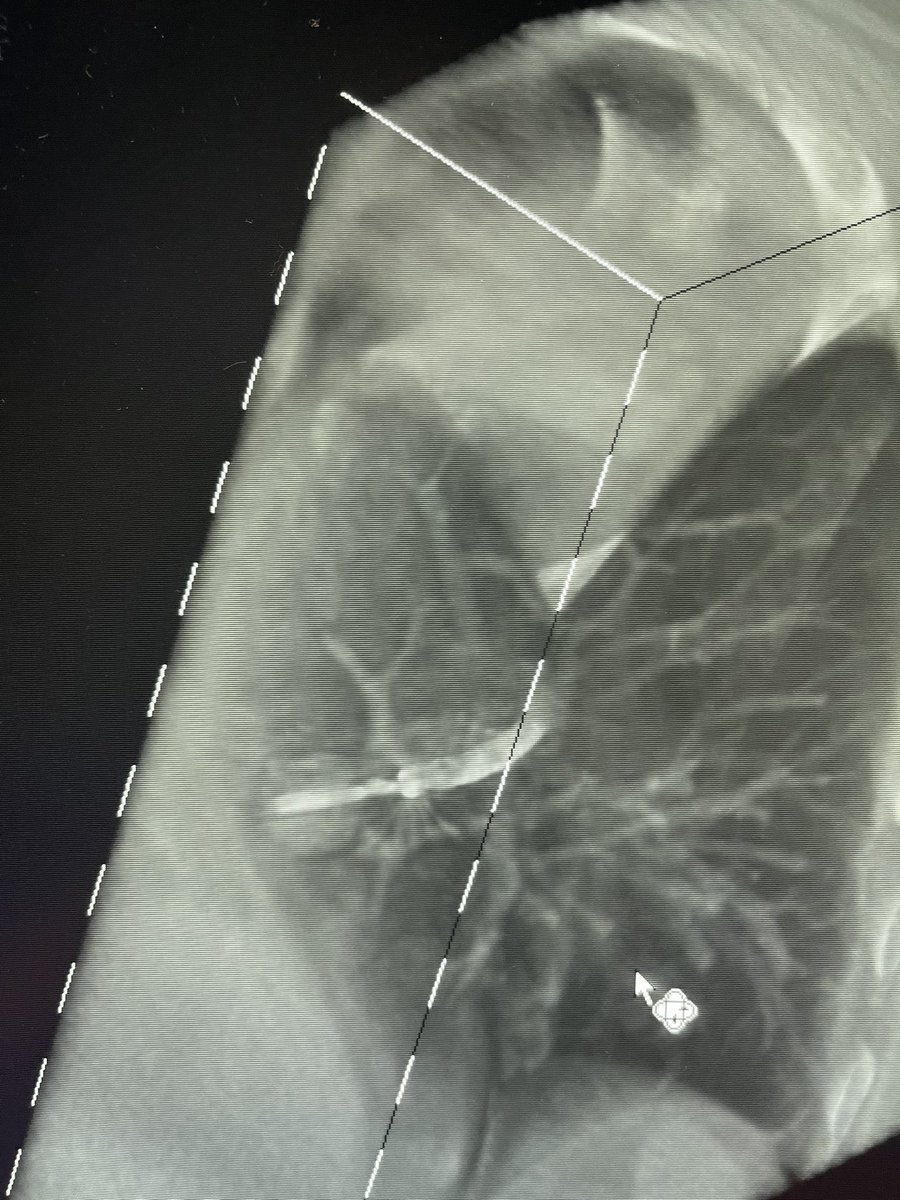

Bhadra & Condra CBCT Bronchoscopy

If you don't like the road you are on, pave a new one: Cone Beam CT Bronchoscopy.